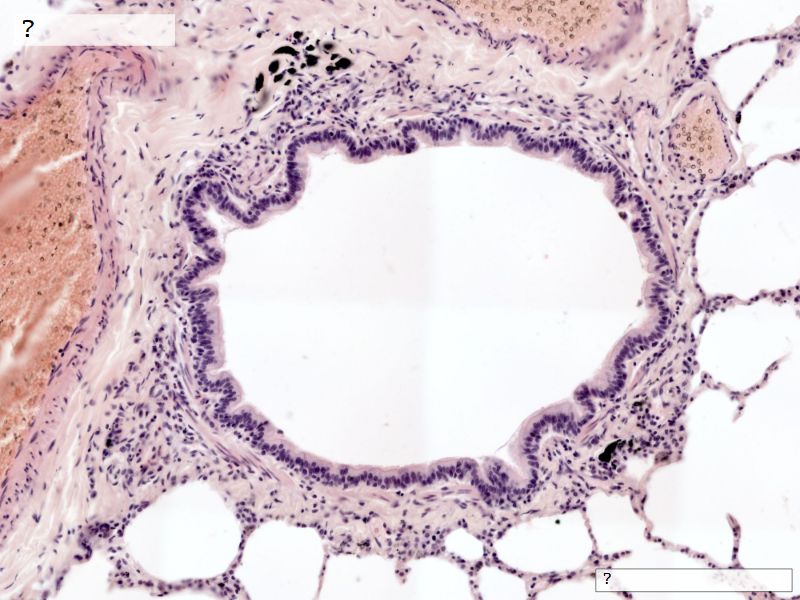

Fill in all the missing labels, and assess as you move through the slides. Answers on the down slide. It is important to do this using pen and paper, and not just glance through the images.